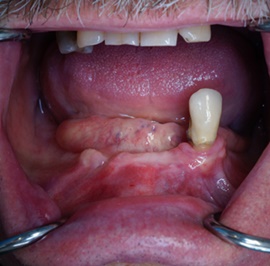

Bezzębie całkowite górne. Początkowo wykonane na mieście mosty całoceramiczne wydawały sie sukcesem, ale po roku pojawiły sie obrzęki i krwawienie z dziąseł. Pacjentka zgłosiła się do leczenia. Usunięto wszystkie zęby w szczęce. Sterowana regeneracja tkanek kości wyrostka, modelowanie kształtu i objętości tkanek miękkich, mosty porcelanowe przykręcane do implantów. Zadowalający wynik anatomiczny i estetyczny.